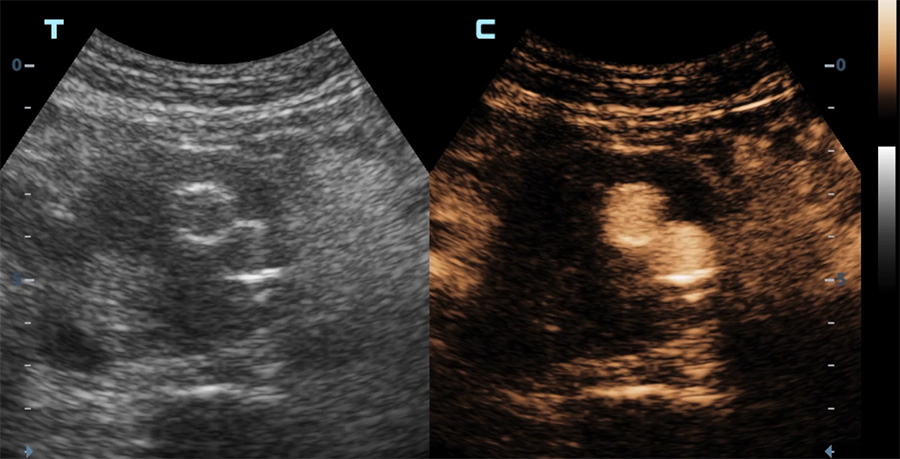

Diffusion du produit de contraste dans le sac anévrismal (vue axiale) en dehors de l’endoprothèse (endofuite)

Diffusion du produit de contraste dans le sac anévrismal (vue longitudinale) en dehors de l’endoprothèse (endofuite)